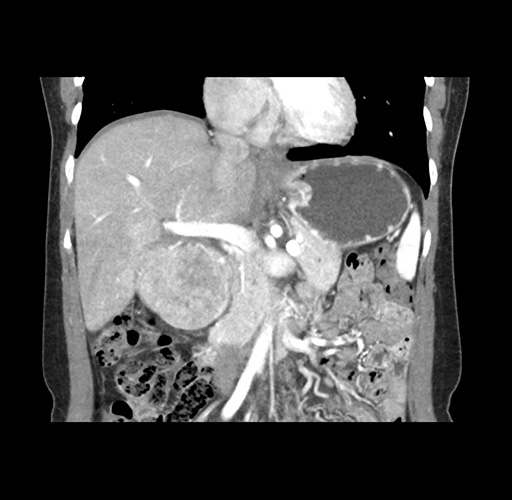

Imaging Analysis

Look through the patient's CT scan to identify any areas of concern for the necessary procedure.

Based on your CT findings, which issue(s) would give reason for "planned slowing down moment(s)" in this case?